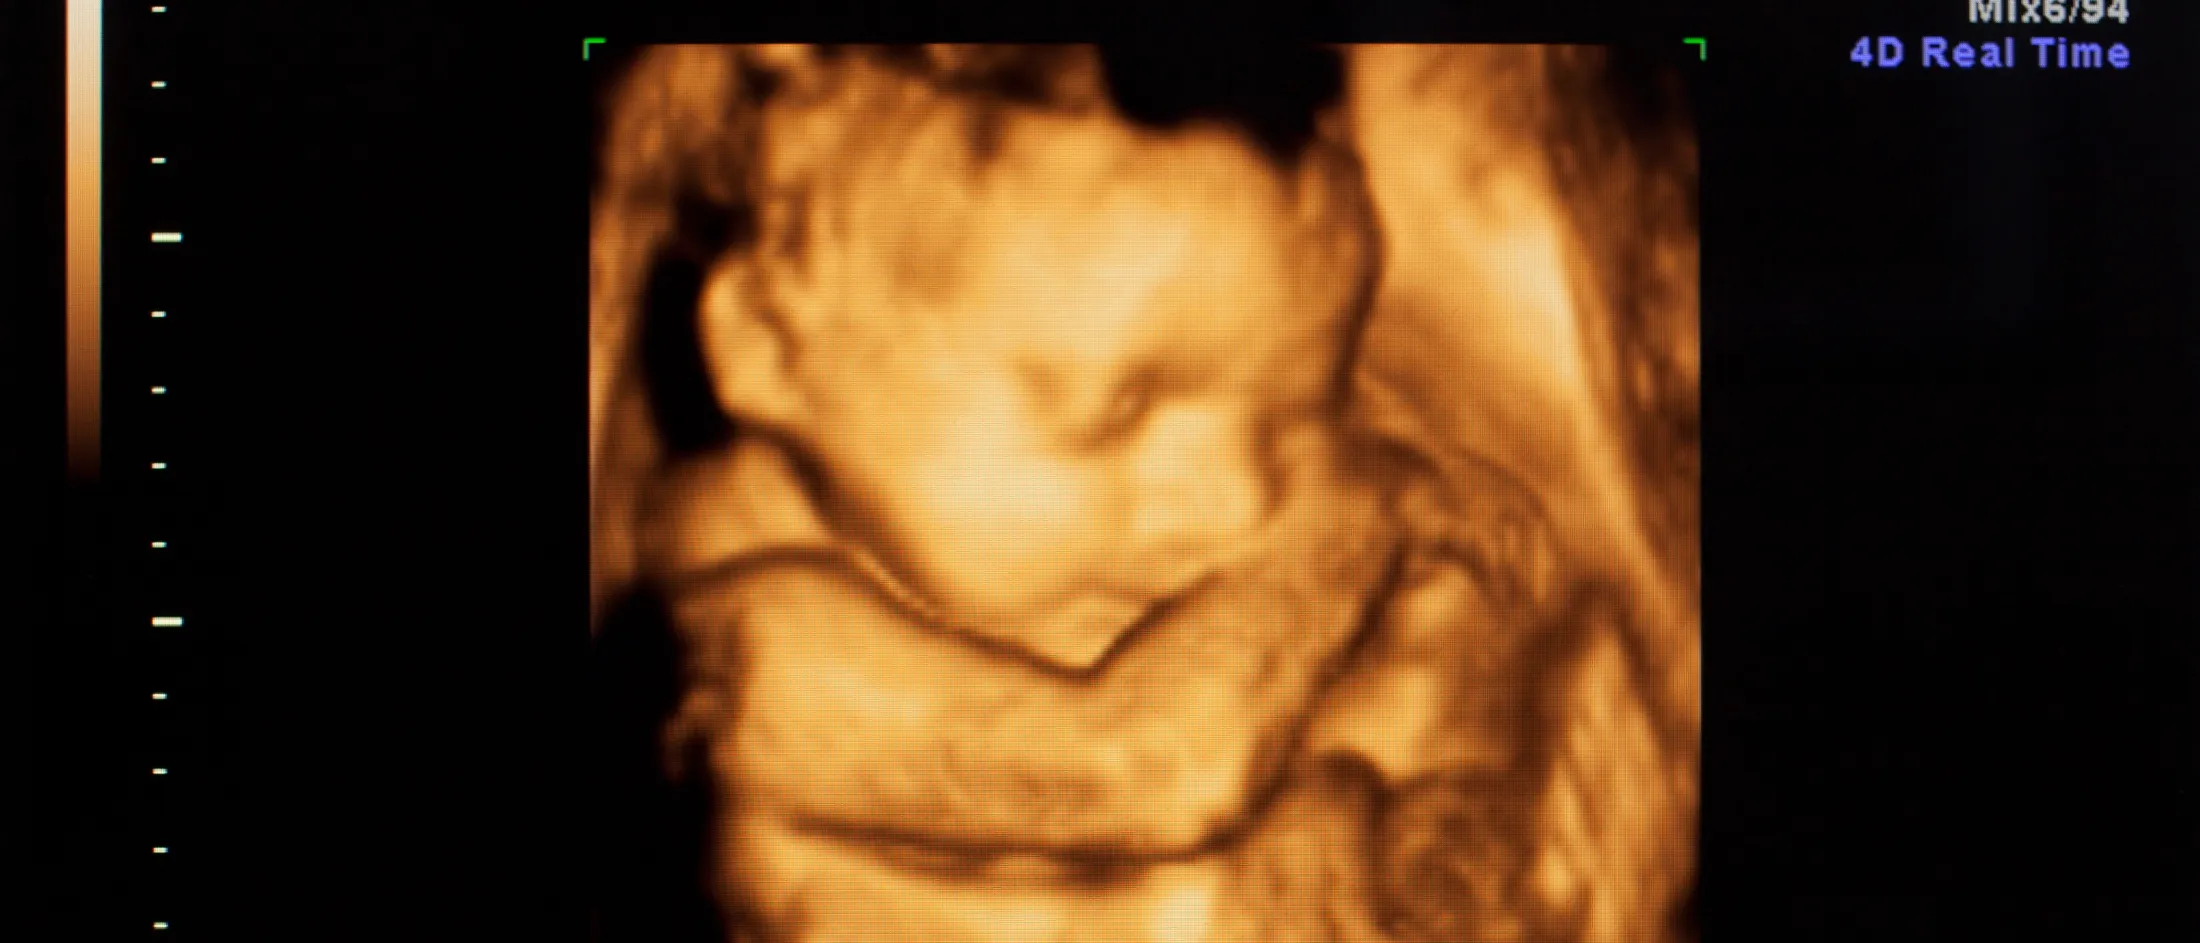

4D ultrasound scan showing a detailed image of a fetus with its arm raised near its face.

Our Program provides comprehensive fetal monitoring and diagnostic evaluations—including biophysical profiles, nonstress tests and Doppler ultrasound studies—to assess fetal well-being, identify potential fetal health risks and guide the development of individualized care plans. We use state-of-the-art imaging technologies such as 3D and 4D obstetrical ultrasound, targeted fetal echocardiography and fetal magnetic resonance imaging (MRI).